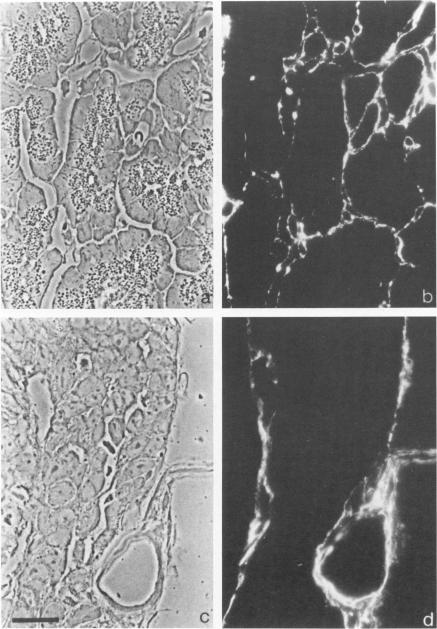

The authors have analyzed the structural relations of a nonmetastatic rat pancreatic acinar carcinoma and contrasted them with those of normal exocrine pancreas in order to better define the role of basement membrane (BM) in early stages of neoplastic disorganization. These studies showed that normal acinar cells rested on continuous BM (containing laminin, heparan sulfate proteoglycan, and Type IV and V collagens) and displayed a polarized distribution of intracellular organelles, cytoskeletal assemblies (concentration of actin within terminal web), and distinct membrane domains (apical leucine aminopeptidase). In contrast, the parenchyma of the pancreatic acinar carcinoma was free of all BM components except for a discontinuous array of laminin. In these regions, acinar tumor cells appeared randomly oriented, displayed actin in uniform cortical distributions, and lost membrane polarity. However, when tumor cells contacted mesenchymally derived connective tissue along tumor capsule and vascular adventitia, they accumulated intact BM and reoriented in a manner reminiscent of normal pancreas. Tumor cell reorganization was observed in the absence of formation of full junctional complexes or normally polarized membrane domains, although leucine aminopeptidase appeared to be excluded from regions of tumor cell surfaces that were in direct contact with BM. The loss of normal epithelial cell-cell arrangements that is the hallmark of early stages of tumor formation could therefore result from failure to match increases in cell number with commensurate BM extension.

作者分析了一种非转移性大鼠胰腺腺泡癌的结构关系,并将其与正常外分泌胰腺的结构关系进行对比,以便更好地确定基底膜(BM)在肿瘤性结构紊乱早期阶段的作用。这些研究表明,正常腺泡细胞位于连续的基底膜上(含有层粘连蛋白、硫酸乙酰肝素蛋白聚糖以及IV型和V型胶原),并表现出细胞内细胞器、细胞骨架组件(肌动蛋白在终末网内集中)以及不同膜结构域(顶端亮氨酸氨肽酶)的极化分布。相比之下,胰腺腺泡癌的实质除了有不连续的层粘连蛋白排列外,没有所有基底膜成分。在这些区域,腺泡肿瘤细胞呈现随机取向,肌动蛋白呈均匀的皮质分布,并且失去了膜极性。然而,当肿瘤细胞沿着肿瘤包膜和血管外膜接触间充质来源的结缔组织时,它们会积累完整的基底膜,并以类似于正常胰腺的方式重新定向。在没有形成完整连接复合体或正常极化膜结构域的情况下观察到肿瘤细胞重排,尽管亮氨酸氨肽酶似乎被排除在与基底膜直接接触的肿瘤细胞表面区域之外。因此,肿瘤形成早期阶段的标志性特征——正常上皮细胞间排列的丧失,可能是由于细胞数量增加与相应基底膜扩展不匹配所致。